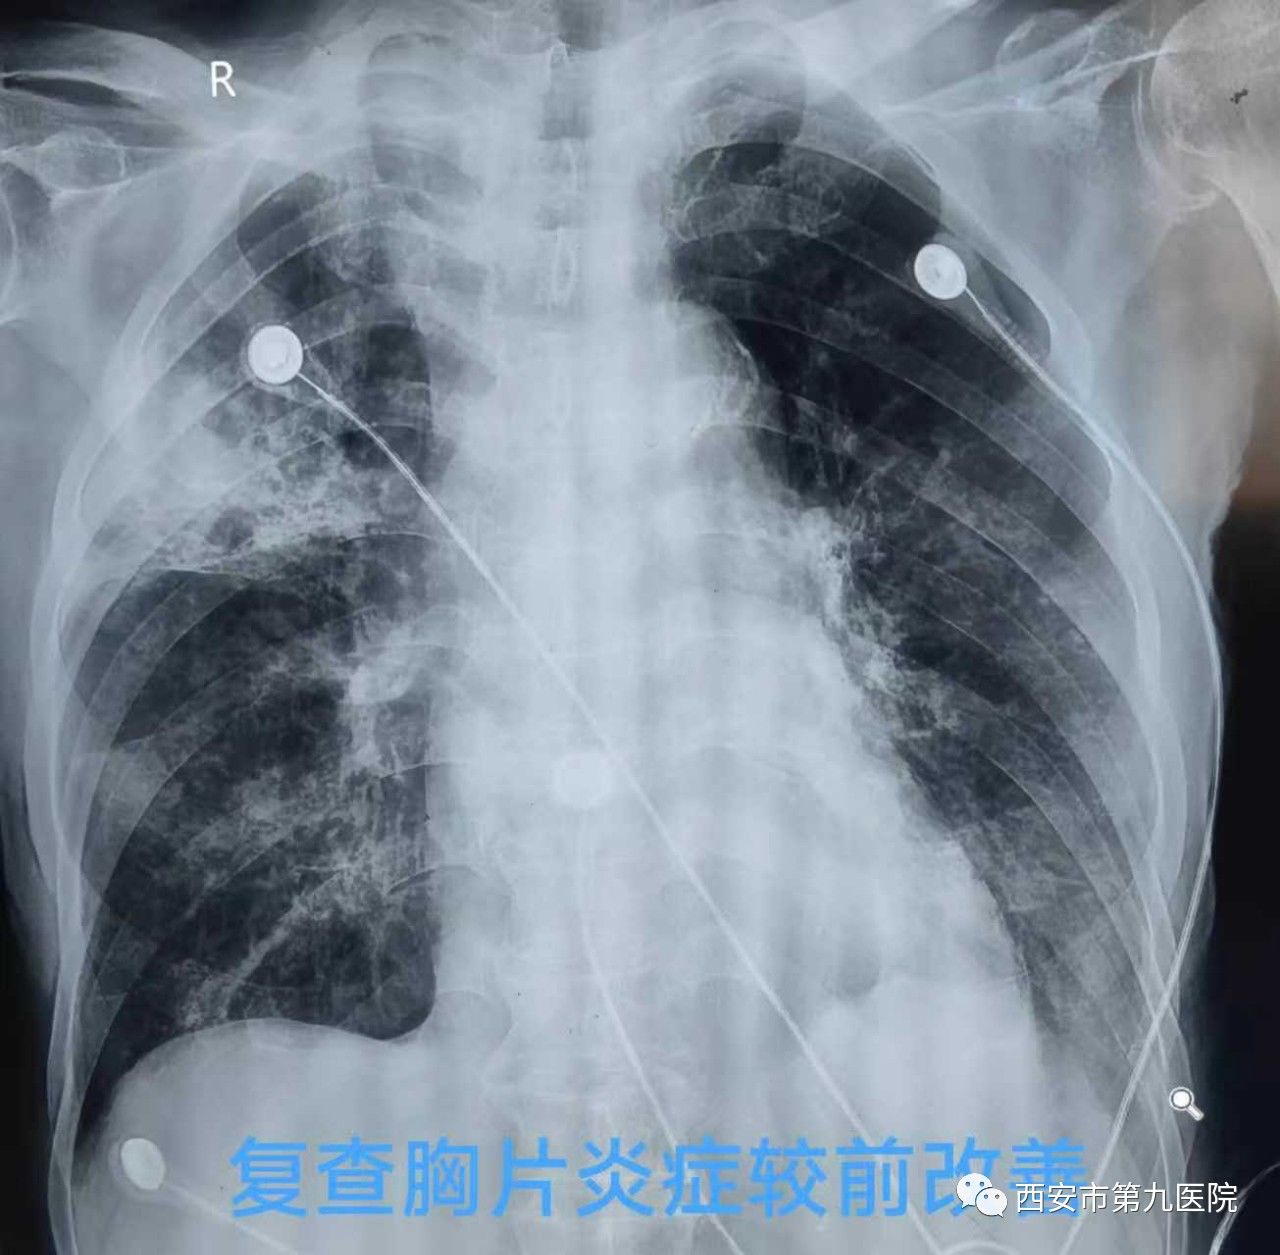

刘晓勇主任带领的团队通过积极给予抗感染、抗病毒药物控制感染,适宜的激素控制炎症、茶碱,氨溴索,雾化等药物化痰平喘,再加上最重要的俯卧位通气,老人终于再一次转危为安。

经过治疗,老人再次醒了过来,这位八旬老人摆脱“白肺”?“白脑”的双重威胁,顺利出院。